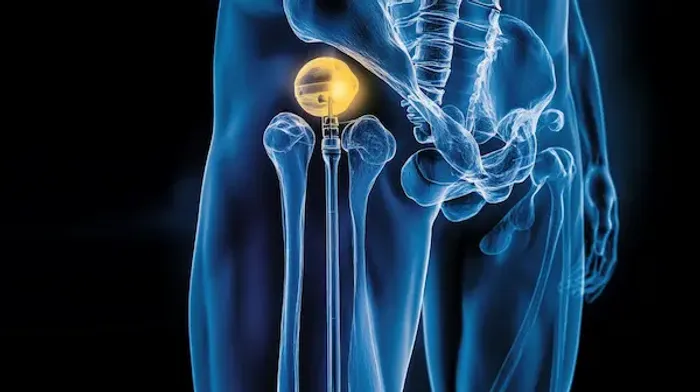

Why Is Positioning Important After Hip Replacement?

After hip replacement surgery, your new joint needs time to heal and stabilise. Certain movements or positions can put stress on the hip, increasing the risk of dislocation (when the ball of the joint comes out of the socket). To prevent this, doctors recommend specific guidelines on how to sit, stand, lie down, and move during recovery.